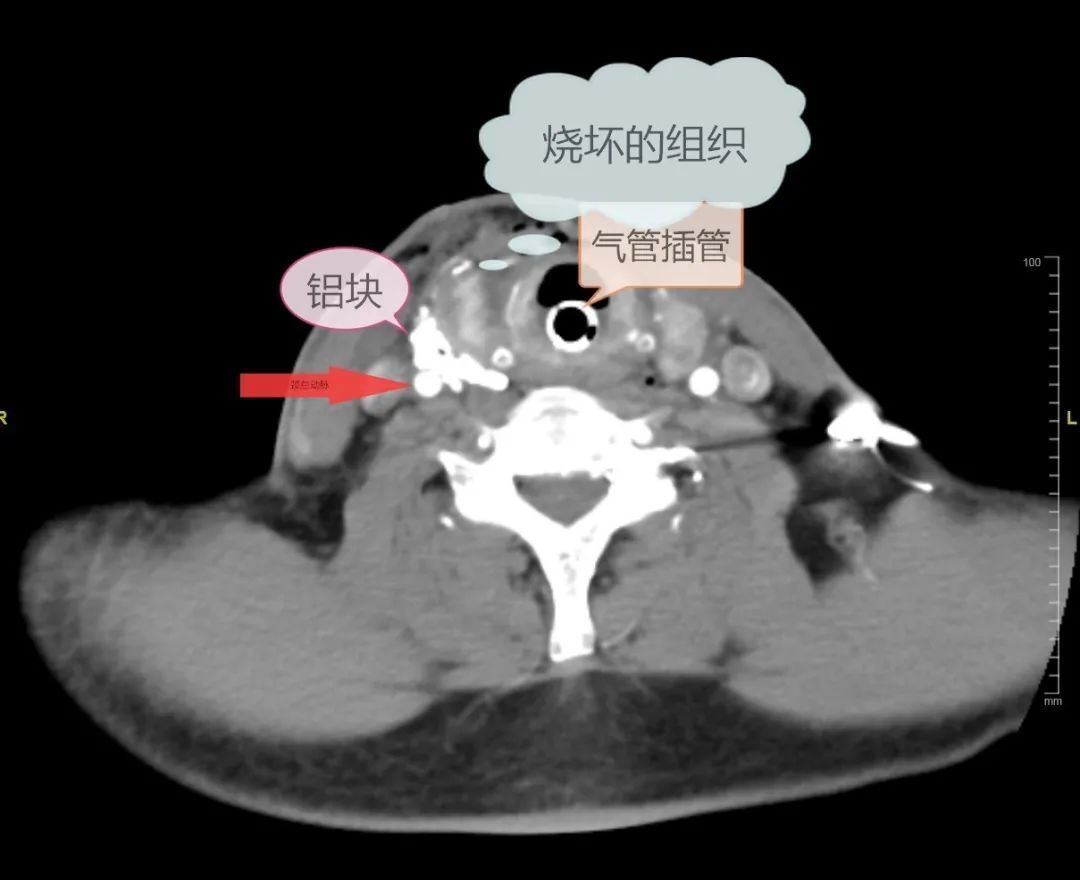

根据CT显示,铝液进入颈部后,“走”出了两条路。一条沿颈内静脉内侧及甲状腺外侧的缝隙,一直往下及往深部贯穿,直达甲状腺后方、锁骨上方位置,另一条通过气管后方间隙到达对侧,沿途留下大大小小的金属铝块。

文章插图

经过支气管镜和CTA颈动脉造影评估,医生们松了一口气,王威的支气管和颈总动脉内膜情况还好。

最担心的动脉大出血

暂时没发生

但忧心的是

铝液凝固时包裹住颈总动脉

像给颈总动脉“穿”了件“铝衣”

颈总动脉很可能已经被高温的铝液烫伤,血管情况不稳定。颈总动脉是头颈部的主要动脉干,这里如果处理不好,患者将面临大出血,给救治带来困难。